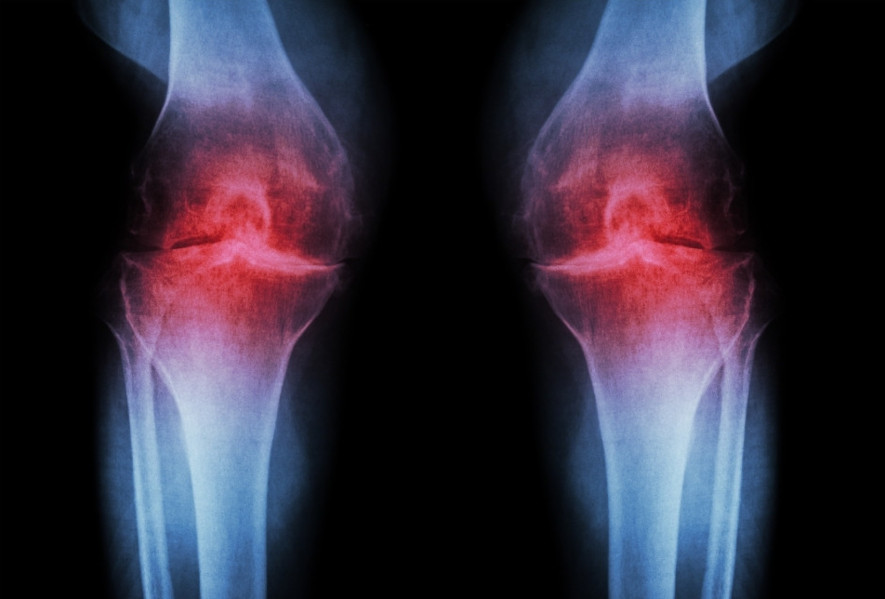

Knäskador